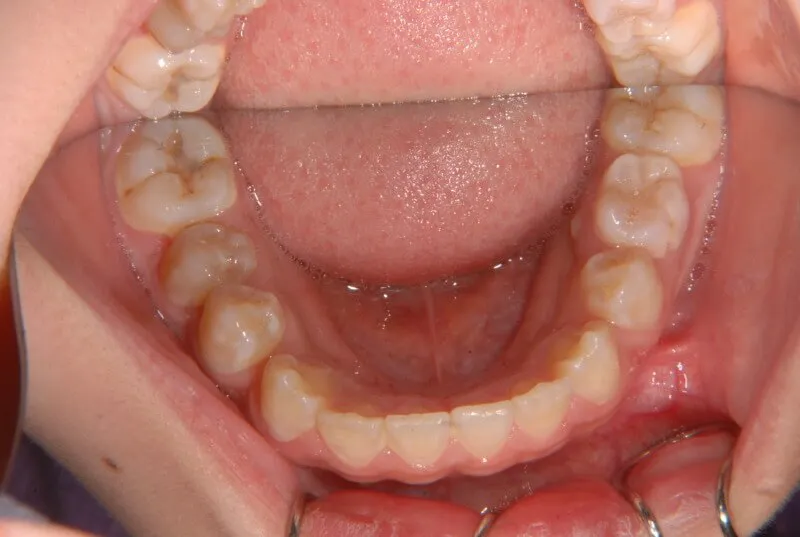

| 初診時年齢 | 小学校1年生(女性) | 主訴 | 受け口 | ||

| 診断名 | 叢生・反対咬合 | 装置名 | 拡大床 | ||

| 抜歯の有無 | 非抜歯 | 治療期間・通院回数 | 2年7ヶ月・21回 | ||

| 費用 | 481,890円(税込) | 費用内訳 | 相談料:1,050円 検査料:46,200円 施術料:210, 000円 装置料:105,000円 保定装置料:52,500円 調整料:3,150円×10回=31,500円 以上 消費税率5% / 調整料:3,240円×11回=35,640円 以上 消費税率8% | ブラケット・ ワイヤー |

付けずに治した |

| 特徴 |

固い食べ物が嫌い 乳歯列が綺麗に並んでいる ゆがんで生えている よく噛まないで飲み込む |

| 状態 |

永久歯が生える隙間がない(叢生) 受け口(口元が出ている/下顎前突/反対咬合) |

| リスク・副作用 |

矯正歯科治療に伴う一般的なリスク・副作用

|